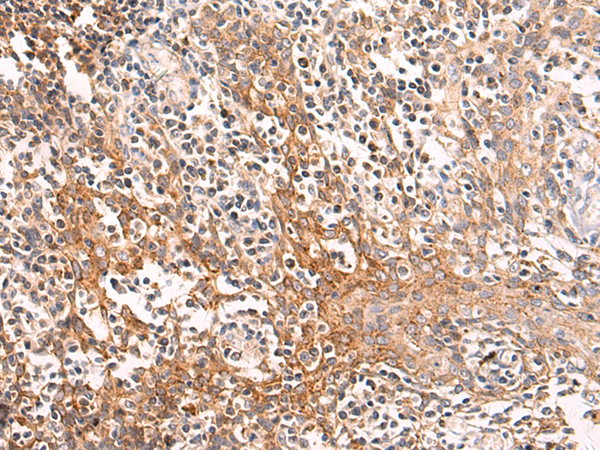

分类: 科研抗体货号: P10567别名: TUG; ASPL; ASPS; RCC17; UBXD9; UBXN9; ASPCR1应用: WB,IHC反应种属: Human, Mouse